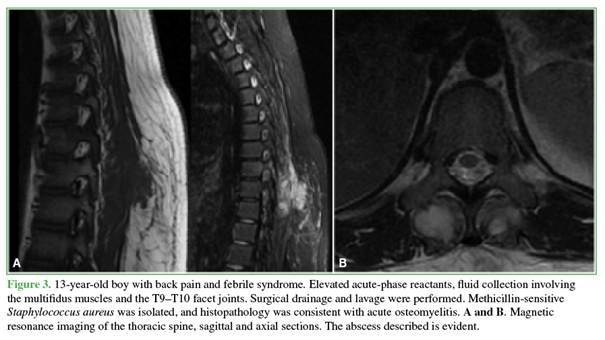

Abscesses associated with spondylitis resolved with antibiotic treatment, whereas the remaining abscesses required surgical drainage, including those in two children whose diagnosis in the emergency department was made exclusively by ultrasound. Staphylococcus aureus was isolated in seven patients (p = 0.001), including four cases of MRSA and three of MSSA (Figures 3-6).

On computed tomography, bone lesions exhibited a lytic or mottled appearance, with asymmetric distribution and poorly defined margins. One patient developed angular kyphosis due to wedging of T11, which required delayed pedicle subtraction osteotomy (Figure 7).

Magnetic resonance imaging showed hypointense signal on T1-weighted sequences and hyperintense signal on T2-weighted and STIR sequences, with gadolinium enhancement. In patients with bone involvement and negative blood cultures, image-guided needle biopsies were performed: three percutaneous transpedicular biopsies, one transfacet biopsy, and one transoral biopsy. In two cases, no pathogen was identified; in two cases, S. aureus was isolated (1 MRSA and 2 MSSA). All specimens submitted for histopathological analysis were classified as acute osteomyelitis (Figures 8 and 9). According to protocol, all specimens were evaluated for tuberculosis (Figure 10).